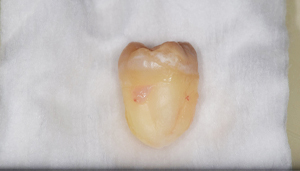

- 抜去歯の写真

3分割して抜歯しました。

- 抜歯した歯の写真